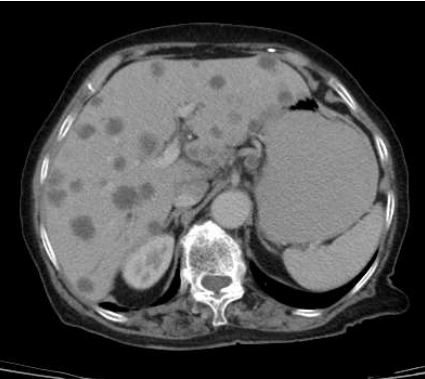

Qual seria a conduta mais apropriada para esse paciente?

O paciente encontra-se assintomático, com performance ECOG 0 e sem icterícia. Qual é a conduta inicial mais apropriada?